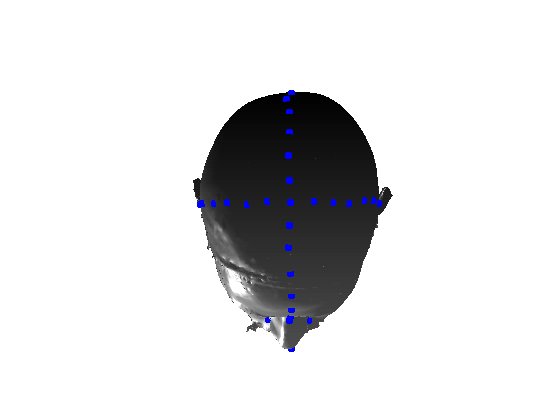

Pose is normalised using the ECN method, and relies on the symmetry plane, ellipse centre and nasion position, as shown in Fig. 25. We then find a set of pseudo-landmarks on the cranial surface by 3D ray projection over a predefined set of angles, as shown in Fig. 26. The same processes are applied to a template mesh of the human head, so that it has the same set of both face and cranium landmarks.

|

|

|